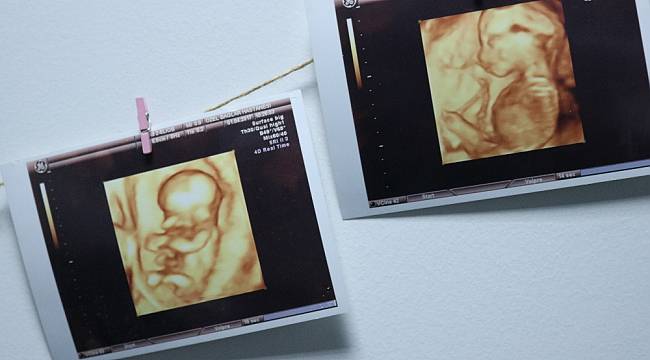

Annelik Heyecani Magazin Haberleri Milliyet